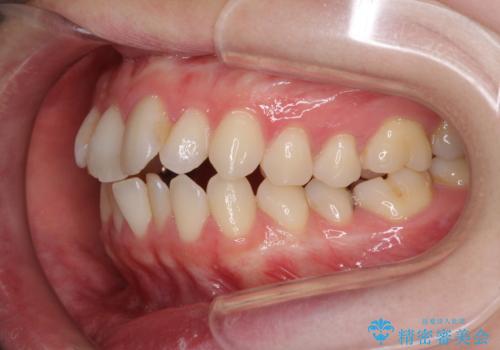

- 前歯のデコボコを気にして来院された患者様です。

下顎が骨格的にずれており、上下正中を合わせることは難しいことが予想されたため、デコボコの解消を主目的として、ワイヤー矯正を行うこととしました。